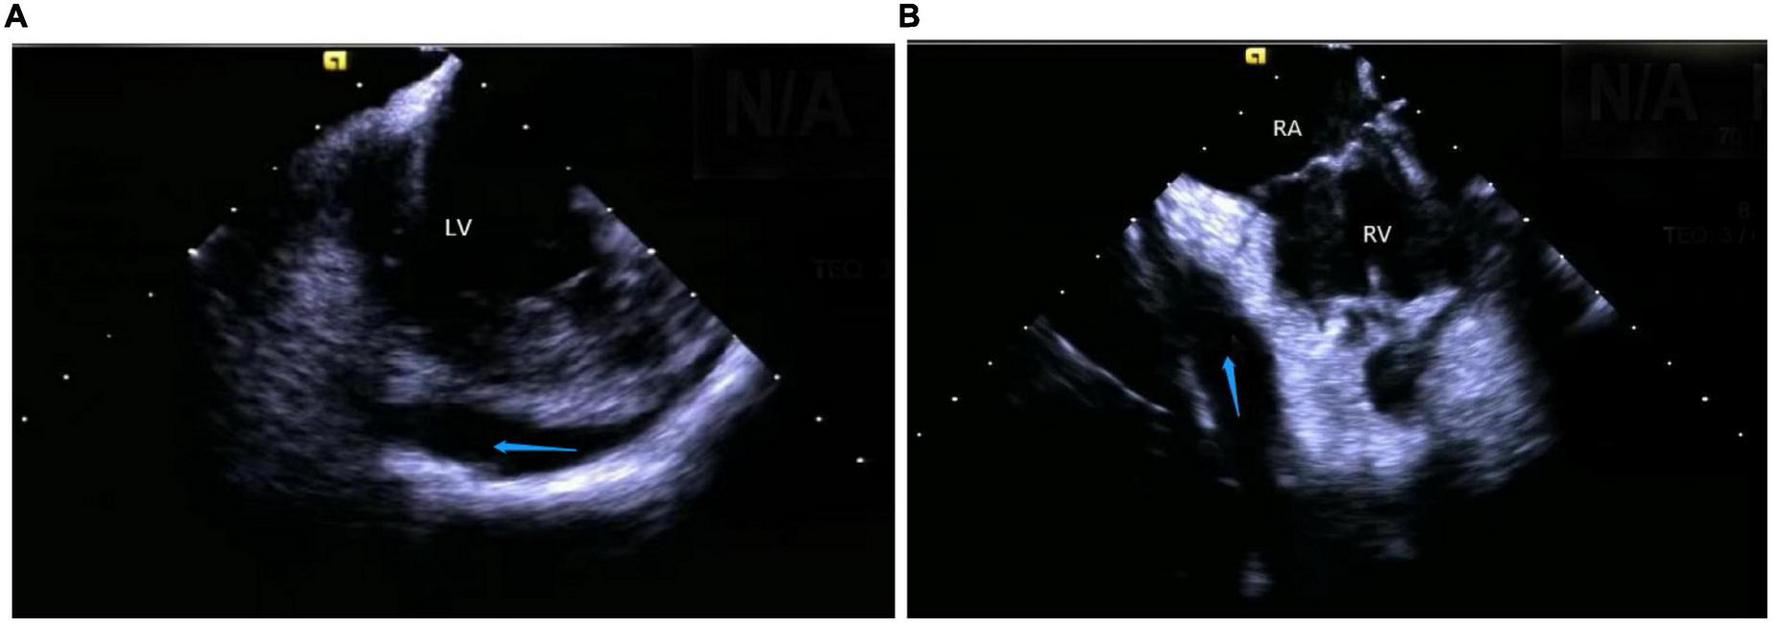

(2) Right atrium operation and view: After positioning the ICE catheter in the mid-right atrium (RA) through the inferior vena cava, the catheter was rotated so that the ultrasound probe points to the center of the tricuspid valve (TV), thereby reaching the HomeView position. This important position provided imaging of the RA, TV, right ventricle (RV), aortic long axis, non-coronary, and right coronary cusps, as well as a small part of the right ventricle outflow tract (RVOT) (Figure 1). From the HomeView position, a clockwise rotation exhibited the RV long axis model, showing the RA, coronary sinus, non-coronary and left coronary cusps, and part of the left ventricle (LV). Further clockwise rotation identified the left atrium (LA) and displayed the LA, RA, coronary sinus, left atrial appendage, mitral valve, and LV, respectively (Figure 2).

FIGURE 2

(A) The clockwise rotation from the HomeView position. (B) The clockwise rotation from the A position. RA, right atrium; CS, coronary cusp; LV, left ventricle; NCC, non-coronary cusp; LCC, left coronary cusp; RVOT, right ventricular outflow tract; LA, left atrium; MV, mitral Valve; LAA, left atrial appendage.

Mostly idiopathic, right ventricular outflow tract arrhythmias are the most common form of clinical ventricular arrhythmias, accounting for about 80% of the total outflow tract ventricular arrhythmias (18). The myocardial tissue of the RVOT anatomically extends to the pulmonary valve and the pulmonary artery, which makes the ablation target location more complex. A previous study suggested that about 90% of the subjects had myocardial extension above the pulmonary valve, whereas nearly half (46%) of the RVOT arrhythmia lesions were located above the pulmonary valve (19). In recent years, inverted U-shaped ablation above the pulmonary valve has been widely popularized due to an increased understanding of the RVOT ablation mechanism (20, 21). ICE technique shows the precise position and relationship between the ablation catheter, pulmonary valve, pulmonary artery, and RVOT defines the position of supra-and subvalvular reflexes, visualizes the adhesion and stability of the ablation catheter and the target tissue in real-time as well as monitors the occurrence of procedural complications like valve perforation (Figure 5). Due to the complex anatomy surrounding RVOT, radiofrequency energy transmitted near coronary arteries can lead to the occlusion of major epicardial vessels like the left anterior descending coronary artery, thereby causing myocardial infarction in some cases (22). Hence, it’s critical to identify the functional status of the coronary arteries. De Sensi et al. (23) and Ho (24) reported several successful cases of inverted U-shaped RVOT under the guidance of ICE. The pulmonary artery, aortic valve, left anterior descending branch, and RVOT were precisely monitored in real-time, thus, avoiding the use of radiography and contrast agents, with no perioperative complications.

FIGURE 5

(A) Anatomic reconstruction of right ventricular outflow tract under ICE. RVOT: right ventricular outflow tract; Blue arrow: pulmonary valve. (B,C) Image of the catheter successfully entering the pulmonary artery under the CARTOSOUND module. (B) Right anterior oblique view; (C) pulmonary artery view. (D,E) Image of the catheter successfully attached to the pulmonary sinus in a reverse U-shape under the CARTOSOUND module. (D) Right anterior oblique view; (E) pulmonary artery view. (F) Successful placement of the catheter above the pulmonary sinus was verified by angiography.